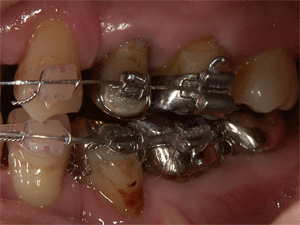

下顎の装置をはずしました。臼歯の隙間は補綴で修復していきます

リテーナーは通常取り外し式を選択するのですが、今回は貼り付けるタイプのものです。いろいろな大きさがあって、その中からあったものをセメントで貼り付けます。内側なので、ほとんど見えることはありません |